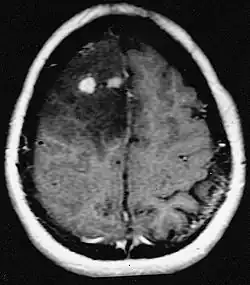

Linfomas primários do SNC

O linfoma primário do sistema nervoso central é responsável por cerca de 2 por cento para 3 por cento de todos os tumores cerebrais em pacientes com um sistema imunológico normal. Ocorrem mais frequentemente em homens com mais de 55 anos até 60 anos acima. Quase metade de todos os linfomas ocorrem em pacientes com mais de 60 anos e cerca de um quarto em pacientes com mais de 70 anos. anos acima. A incidência parece aumentar com a idade, mas a razão ainda não é clara. Pacientes com sistema imunológico enfraquecido correm maior risco de desenvolver linfoma do SNC, portanto, aqueles que tiveram um transplante de órgão têm uma imunodeficiência congênita ou doença autoimune ou estão infectados com o vírus da imunodeficiência humana. Os linfomas cerebrais associados ao HIV estão associados ao vírus Epstein-Barr, particularmente em pacientes com contagens de linfócitos CD4 abaixo de 500 células por milímetros cúbicos no sangue. A maioria dos linfomas do SNC são linfomas difusos de grandes células B.

Os pacientes sofrem de uma variedade de sintomas característicos de uma lesão maciça focal ou multifocal. A RM geralmente mostra tumores com realce homogêneo de contraste dentro da substância branca periventricular profunda. Multifocalidade e realce não homogêneo são típicos para pacientes com sistema imunológico enfraquecido. A análise do linfoma do SNC é extremamente importante no diagnóstico diferencial das neoplasias cerebrais. Ressalta-se que a administração de corticosteróides pode levar ao desaparecimento completo do realce, dificultando o diagnóstico das lesões. Consequentemente, se o linfoma do SNC for considerado no diagnóstico diferencial, os corticosteróides devem ser evitados, a menos que o efeito de massa cause um problema sério e imediato no paciente.

A biópsia da lesão suspeita é crucial. Ao contrário do linfoma sistêmico de grandes células B, no qual tanto a quimioterapia quanto a radioterapia são eficazes e o tratamento de lesões localizadas é curativo, o linfoma do sistema nervoso central geralmente responde à terapia inicial, mas depois recorre. Assim como no linfoma sistêmico, o papel da cirurgia limita-se principalmente à obtenção de amostras de tecido apropriadas para o diagnóstico.

No passado, a radioterapia era administrada em todo o cérebro (panencefálico). A sobrevida mediana é de cerca de 12, mesmo com lesões localizadas Meses. A recorrência geralmente afeta o local da lesão anterior, bem como outras regiões. As respostas à quimioterapia são mais promissoras. Ensaios clínicos nos quais o metotrexato em altas doses foi usado como primeiro tratamento e a radioterapia foi adiada até o momento da recidiva ou progressão mostraram melhor sobrevida global do que a radioterapia isolada. Ainda mais eficaz foi a combinação de metotrexato, vincristina, procarbazina, metotrexato intratecal, citarabina e radioterapia panencefálica e citarabina, ou o uso de quimioterapia intra-arterial com metotrexato intra-arterial, ciclofosfamida injetada por via intravenosa e etoposídeo após modificação do sangue- barreira cerebral com manitol. A sobrevida mediana na terapia com metotrexato foi de 24 até 40 meses muito maior do que com radioterapia isolada (intervalo de 24 até 40 meses). Em alguns casos, a radioterapia é utilizada apenas para recidivas quando há uma regressão inicial com a quimioterapia. Casos de longa sobrevida também foram relatados sem radioterapia.

A radioterapia panencefálica está associada a um alto risco de desenvolver demência ou leucoencefalopatia. Esse risco pode ser reduzido desenvolvendo estratégias eficazes de controle do tumor que evitem a radioterapia panencefálica. A terapia inicial para pacientes com sistema imunológico comprometido é reduzir as causas da imunossupressão. O prognóstico para esses pacientes geralmente é pior do que para pacientes que têm um sistema imunológico normal. Devido a infecções tumorais concomitantes e uma condição física geralmente abaixo do ideal, a quimioterapia muitas vezes não pode ser realizada nesses pacientes imunossuprimidos. Tal como acontece com outros tumores cerebrais, a resposta aos tratamentos depende da idade e da condição física.